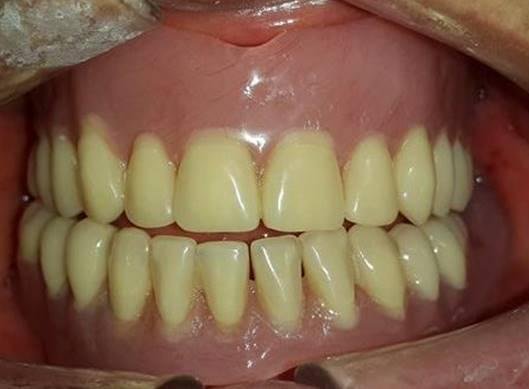

TRATAMIENTO FINAL

Prótesis total superior e inferior elaboradas con Eclipse

EVOLUCIÓN

7 días después

"Me siento mucho mejor, ahora si puedo comer" Paciente